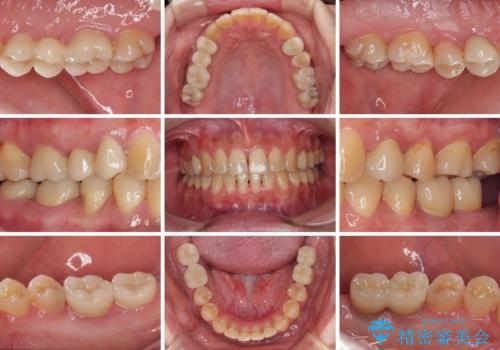

- 奥歯に問題が多くて困っているとのことで来院された患者様です。

開咬により奥歯のみが接触している状態で、前歯部にほとんど接触のない状態で、奥歯に非常に負担のかかる咬み合わせでした。

また、欠損や根管治療の必要な歯など、むし歯による問題も多く散見されました。